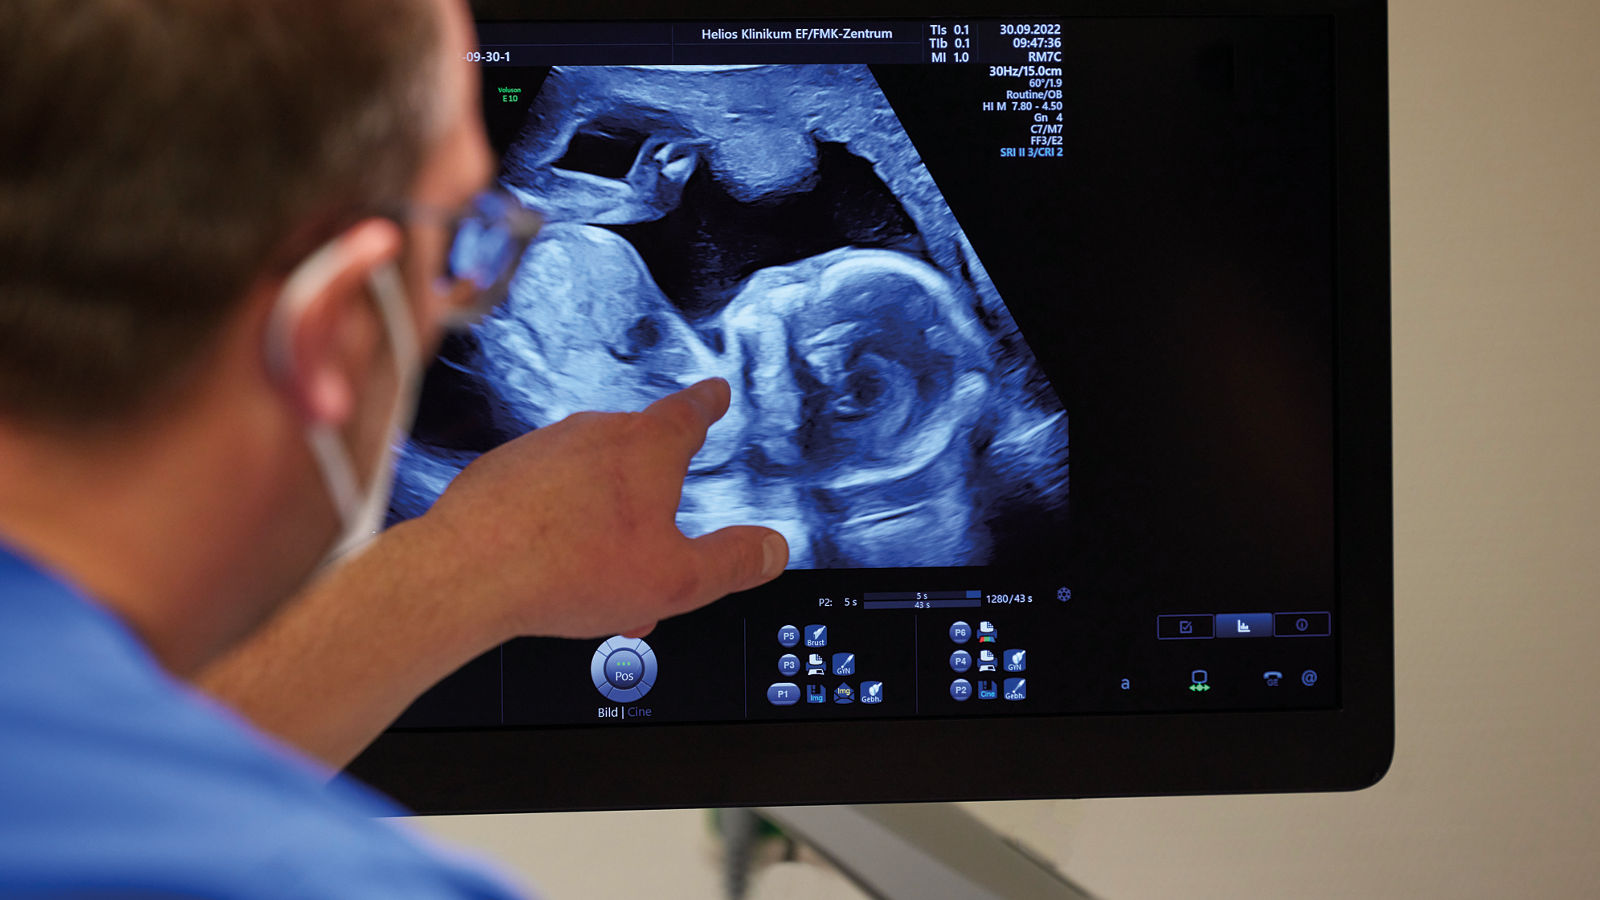

Untersuchung Ultraschall

Für Ellas Familie beginnen die Veränderungen schon in der Schwangerschaft, denn auf allen Ultraschallbildern bleibt das kleine Mädchen immer ein wenig hinter den Größenvorgaben zurück. Doch sie entwickelt sich konstant, also gibt es erstmal keinen Grund zu großer Sorge.